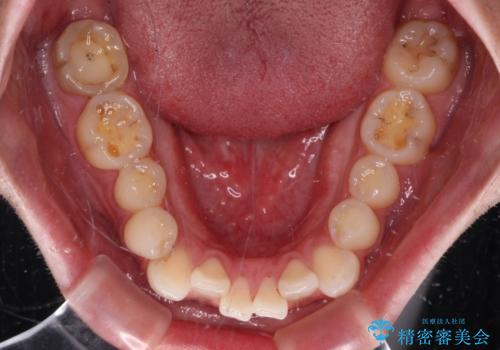

- 上下顎歯列のデコボコを改善したいとのことで来院された患者様です。

自己管理の大変なインビザラインや、目立つ表側のワイヤー矯正は避けたいとのことで、

上顎だけ裏側装置のハーフリンガルにて矯正しました。